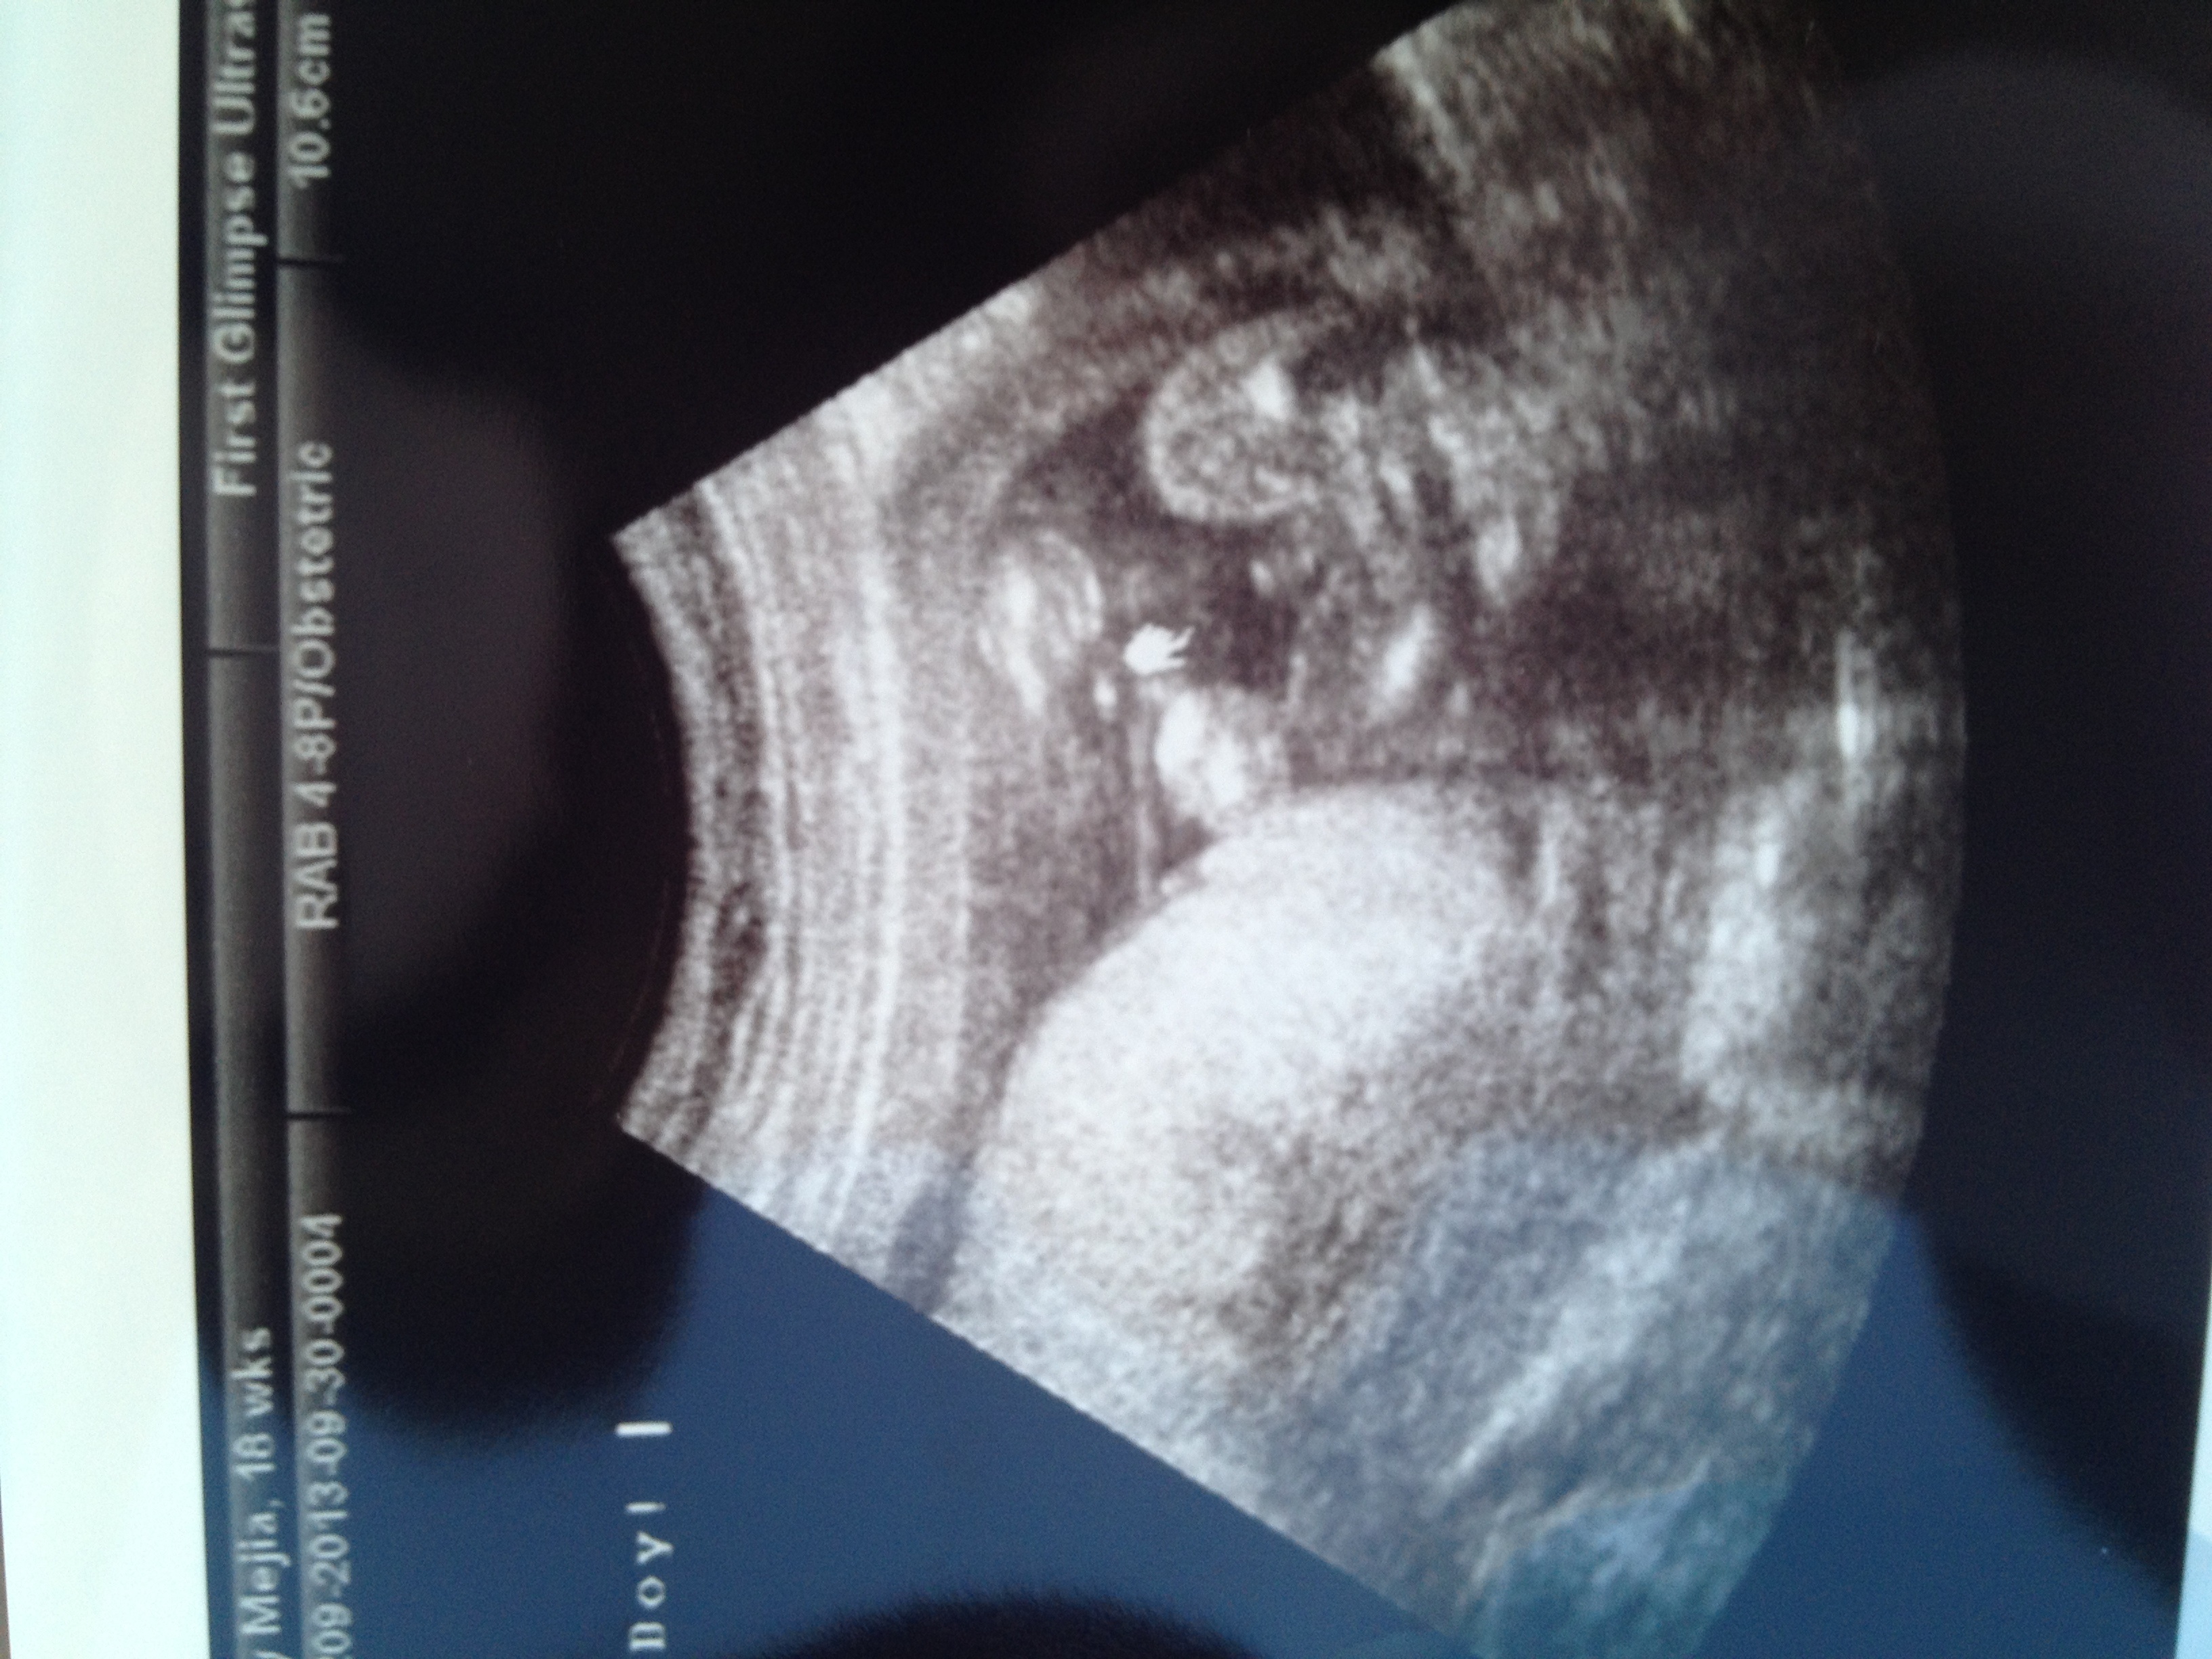

We just got these 2 u/s pics yesterday at our 17 week appointment. I realize they aren't the greatest, but my doc said based on what he saw he'd guess girl. He did say he wasn't 100% until we had our 20 week anatomy scan which will be much more hi-res than his equipment. Boo, 3 weeks feels like forever. SO in the meantime, anyone care to take a guess?

Baby GIRL due 12/26

I honestly can't say. I agree with pp, there isn't three lines, but there isn't a penis either.